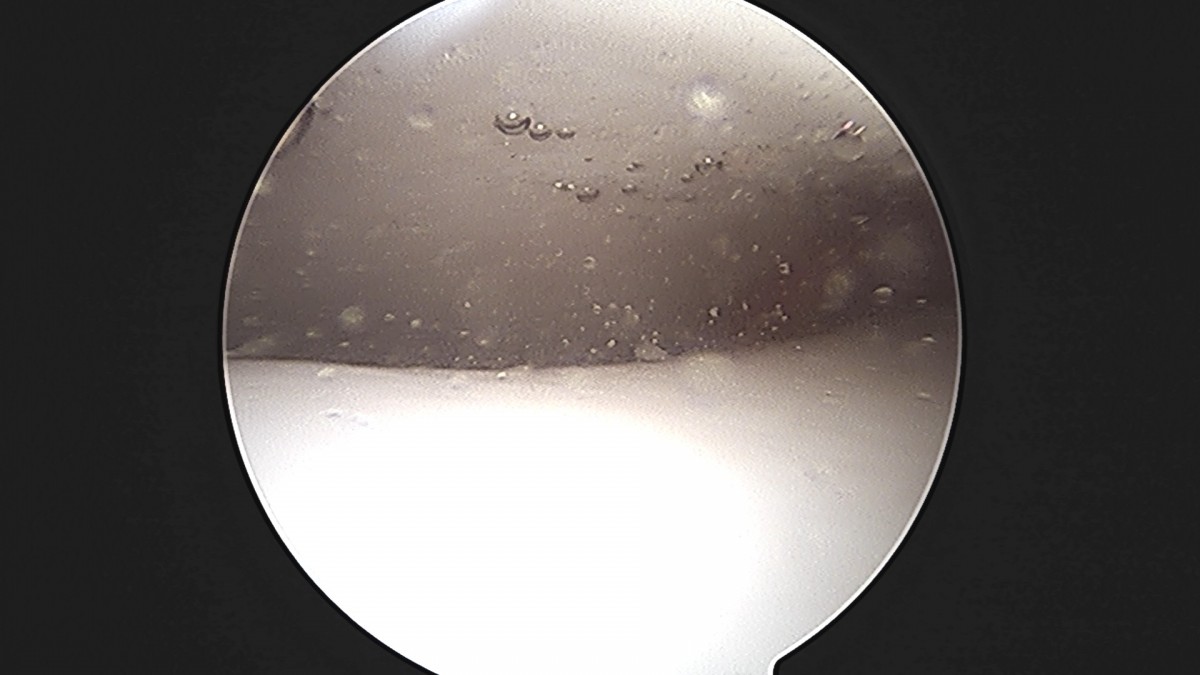

정지영원장님 발목 인대 봉합술 채이O 환자

작성자 최고관리자 댓글 0건 조회 718회 작성일 25-09-16 17:02